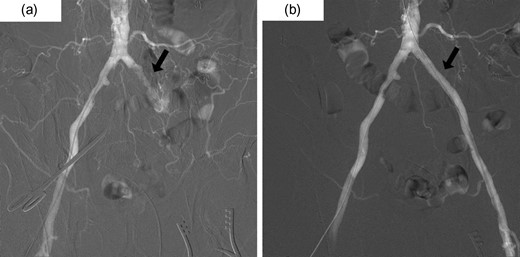

He underwent an elective laparoscopic abdominoperineal resection with a lithotomy position. There was no vascular injury or compression with laparoscopic forceps as far as we were able to recognize retrospectively based on the laparoscopic video and the memory. The duration of surgery was 4 hours and 48 minutes. Blood loss was estimated 100 ml, the urine volume was only 50 ml during the operation. In-out balance during operation divided body weight and time of operation was 6.38 ml/kg/h. The patient reported a severe pain in the left leg, when he woke up post-operatively. The left leg was pale and cold, associating sensory abnormality and motor dysfunction; left pedal and popliteal pulses were absent. A CT scan revealed the contrast interruption of left common iliac artery (CIA) over 11.5 cm and suspected to be due to an arterial thrombosis (Fig. 2). Under the local anesthetic technique, the left femoral artery was exposed and performed thrombectomy with a 5Fr Fogarty catheter. After a new clot was removed, aortography revealed persistent stenosis in left iliac artery. Consequently, a Percutaneous transluminal angioplasty (PTA) with stent (Express LD 8 × 37 mm) was added (Fig. 3) via left femoral artery. Blood perfusion in his left leg improved markedly immediately post PTA. The patient was transferred to the intensive care unit for two days due to the complications with a rhabdomyolysis (creatinine phosphokinase up to 23 598 IU/l). The patient started walking 5 days post-surgery, however, the patient was left with the numbness in his left lower leg. A heparinization had been commenced on the postoperative day 1, then this was switched to the cilostazol prior to the discharge for home. We note that the patient continued reporting the left lower leg numbness even one year past the surgery.

(a) Pre-intervention aortography demonstrating occlusion of the left CIA and the development of collateral circulation in left pelvic cavity. (b) Post-intervention aortography showing improvement of occlusion by a percutaneous transluminal angioplasty (PTA) with stent.